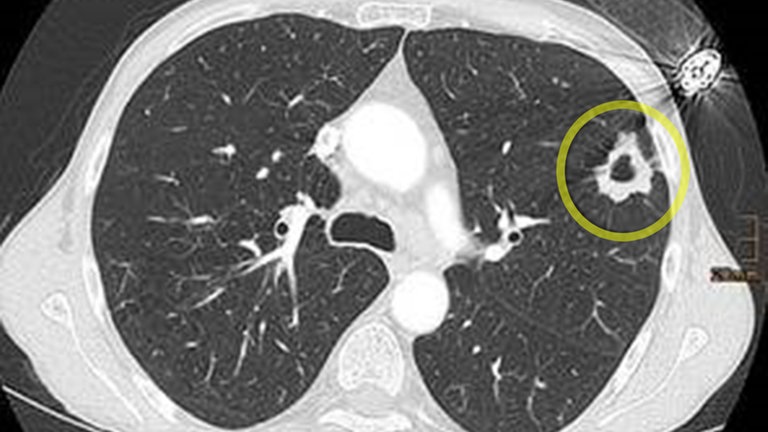

In Deutschland erkranken jedes Jahr etwa 57.000 Menschen an Lungenkrebs. Viele von ihnen haben lange geraucht. Das Universitätsklinikum Freiburg hat als erste Klinik in Baden-Württemberg die Genehmigung erhalten, ein Lungenkrebsscreening per CT für starke Raucherinnen und Raucher anzubieten.